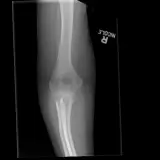

Over 2,100 interactive radiology cases, curated by radiologists for your level of training. Scroll, window, and view cases full screen — just like on PACS. Click linked findings in each writeup to jump straight to them on the image. Cases include sample reports, a focused discussion section, original illustrations, and videos.

Casos totalmente interativos com as ferramentas que você espera em um PACS — rolagem, ajuste de janela, zoom, movimentação, medidas, ROIs e modo de tela cheia.

Anotações detalhadas destacam os achados principais diretamente nos casos. Clique nos achados vinculados nas descrições dos casos para ir ao local exato no exame.

Role, movimente, ajuste janela e amplie como em uma estação PACS do trabalho